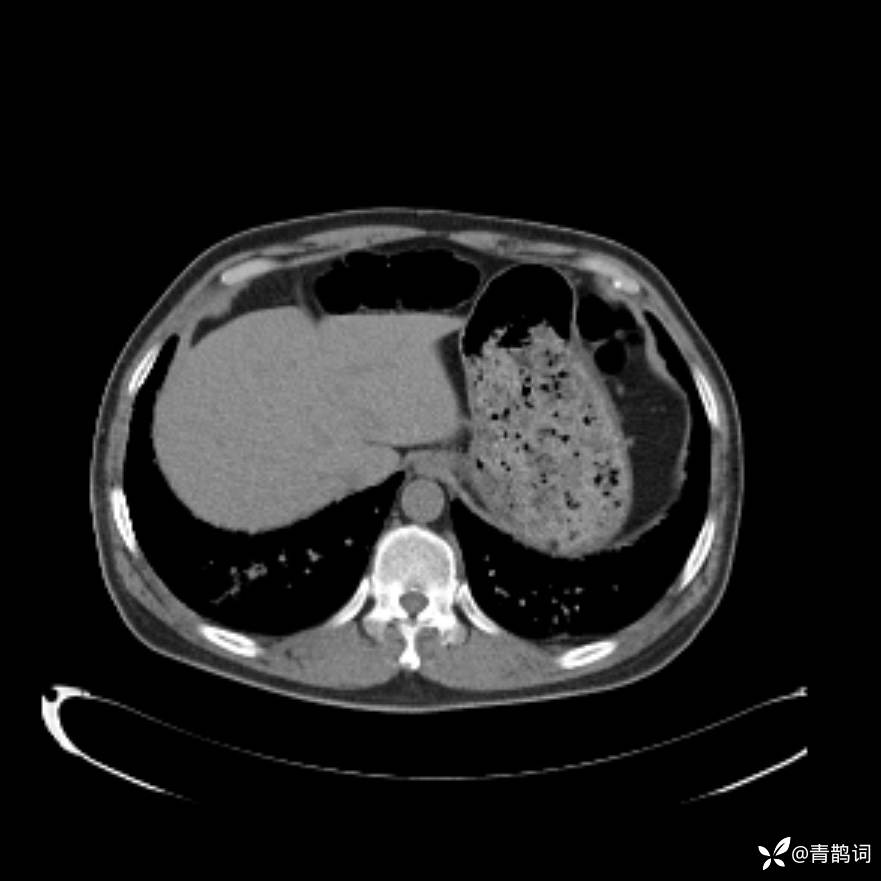

患者年龄:30岁。

患者性别:男。

简要病史:左颜面部肿胀2年,反复咳嗽咳痰,逐渐加重。

辅助检查

结合病史及影像学表现,期待评论区各位老师各抒己见~